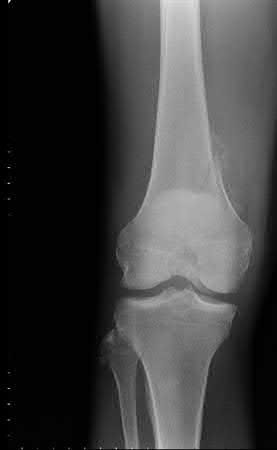

A 64-year-old woman is thrown off a horse, sustaining the injury shown in Figures A and B. She undergoes surgical fixation as seen in Figures C through E. What is the most commonly reported complication of this procedure?

1) Axillary nerve injury

The patient in the scenario has a 2-part proximal humerus fracture treated with a locking plate as seen in Figures A-E. The most common complication with the use of this implant is screw penetration. The terms screw cut out and penetration are often used interchangeably in the literature with cut out appearing more frequently in reports regarding intertrochanteric fractures.

Owsley et al retrospectively reviewed 53 proximal humerus fractures treated with locking plates and the same post-operative protocol. The most common complication was screw cut out or penetration, followed by varus displacement. They concluded that 3 and 4-part fractures in patients over 60 years have a higher incidence of failure.

Agudelo et al retrospectively reviewed 153 patients at a level-one trauma center treated with proximal humerus locking plates, investigating modes of failure for the implant. They determined that varus malreduction (head-shaft angle